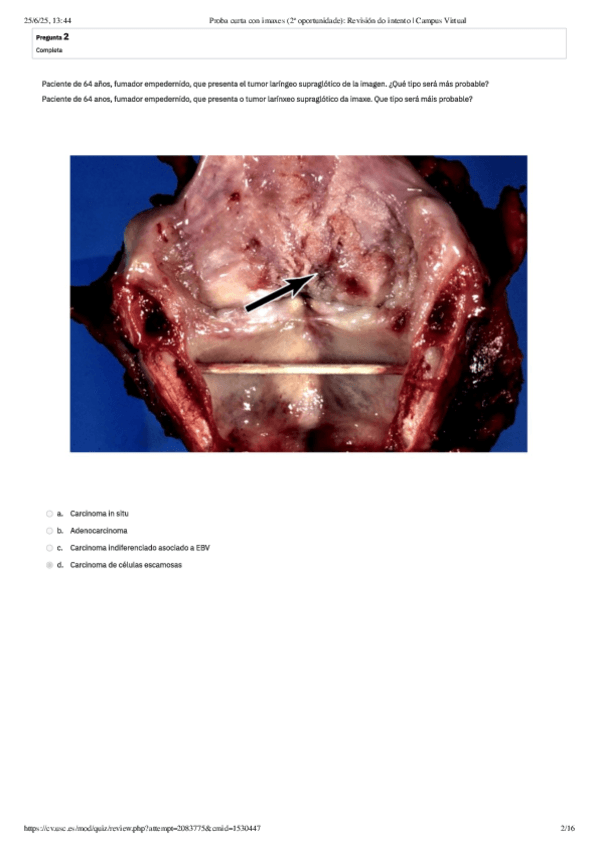

He publicado nuevos examenes de 3º Anatomia Patològica Especial: Preguntas-PATOLOGIA-DE-LA-VIA-AEREA-SUPERIOR.pdf

2 páginas